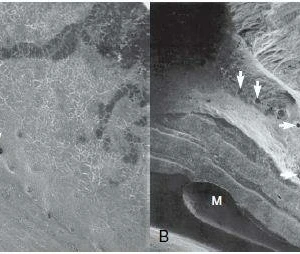

Sau khi gây tê tại chỗ, răng giả đã được cắt và loại bỏ. Sau đó, xương ổ răng vẫn hiện diện quanh implantl. Trong lần điều trị này, điều chỉnh chính xác abutment được thực hiện và xác nhận với X-quang. Khu vực cấy implant được để lành thương mô mềm. Sau 8 tuần lành thương mô mềm, phẫu thuật ghép mô liên kết (CTG) đã được lên kế hoạch với vạt bao, vạt nhú lợi xoay xiên (oblique rotated papilla flap) bằng cách sử dụng các đường rạch dưới lợi viền. Kĩ thuật chia tách tạo khả năng di động thích hợp cho vạt niêm mạc. Các phần lợi viền phía cổ được loại bỏ. CTG được lấy bằng kỹ thuật loại bỏ biểu mô. Để bù đắp thiếu hụt niêm mạc, CTG được gấp đôi và khâu bằng với vật liệu tự tiêu trước khi khâu cố định. CTG đã được cố định mặt môi, ôm lấy bề mặt abutment. Vạt niêm mạc tự do, thụ động, căng được khâu.

Sau khi nhổ răng, mô hạt đã được loại bỏ cẩn thận. Khoan xương phía khẩu cái cung cấp sự ổn định chính và đặt phục hình tạm thời. Để bảo vệ các đường cong phía môi, khoảng trống giữa bản xương phía môi và implant được ghép với xương bò khử khoáng. Phục hình tạm thời được gắn vào implant tại lực torque 15 Ncm.